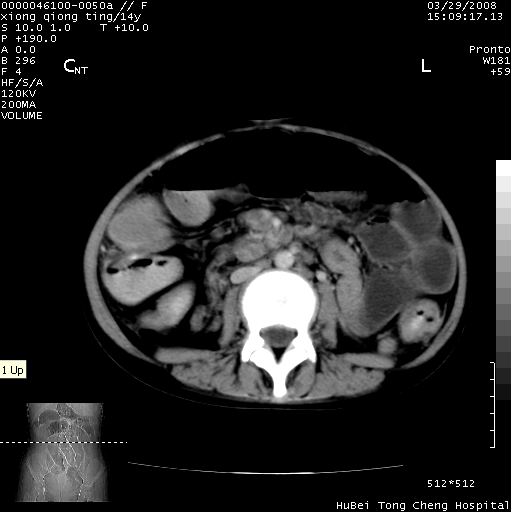

中下腹及盆腔ct轴位平扫+增强扫描(层厚10mm,螺距1.0,重建间隔10mm),图像如下:

(注:患儿检查当日上午9时口服胃肠道对比剂,下午3时许行ct扫描检查,未行对比剂直肠保留灌肠,检查当日患儿腹泻)

中下腹及盆腔ct轴位扫描(ps+ce)提示:腹部肠管明显充气扩张,并见数个不同宽度之气液平面;疑不全性肠梗阻或肠郁张。临床会诊考虑为患儿腹泻,肠郁张所致;后来未经特殊处理,患儿大便恢复正常,亦无腹胀。

临床出院诊断:1)结核性腹膜炎。2)腹膜后淋巴结结核。3)脂肪肝。